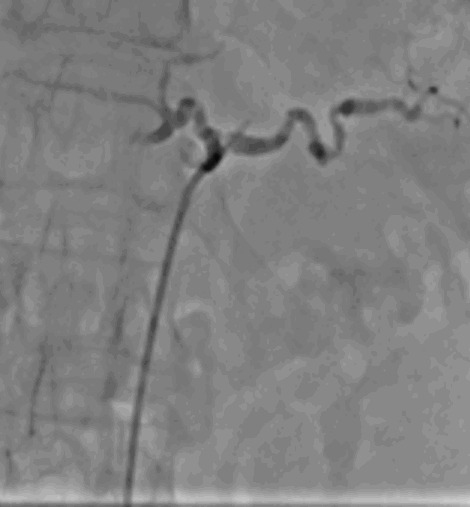

“Our abstract reports findings from a first-in-human proof-of-concept study evaluating transvascular RF denervation of the celiac plexus in patients with refractory pancreatic cancer–related abdominal pain,” said researchers from AKFA Medline Hospital in Uzbekistan, the University of British Columbia, and Autonomix Medical, Inc. “The goal was to assess procedural feasibility, safety and early clinical outcomes.”

In this prospective study, 19 of 20 enrolled patients underwent successful treatment, corresponding to a 95% procedural feasibility rate, researchers said. This total population group observed significant reductions in pain as early as 24 hours following the procedure, with mean pain reductions exceeding 40% through three months of follow-up. Importantly, there were no device- or procedure-related serious adverse events.

“100% of subjects who underwent a femoral access procedure responded to treatment,” researchers said. That group had a 59% reduction in pain, and 100% of responding patients were opioid-free within 7 days. At 4-6 weeks, 73% remained opioid free.

Autonomix is developing a catheter-based sensing and RF ablation platform designed to improve how physicians identify and treat peripheral nerves.